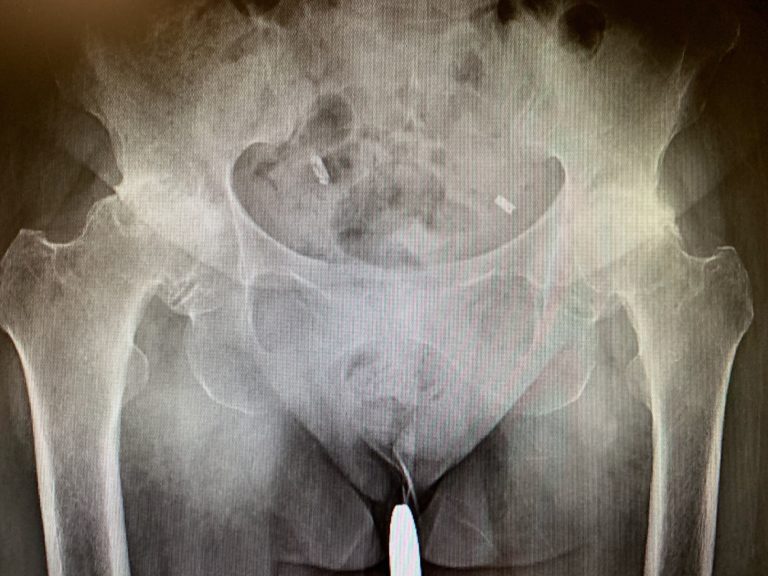

IMPLANTS USED: 52 mm cup with 6.5 mm screw, 25 mm in length with a 0-degree polyethylene with a 127-degree neck stem with a ceramic femoral head 36 mm minus 2.5. DESCRIPTION OF PROCEDURE: The patient was brought to the operating room after obtaining informed consent, finding the correct surgical site.

Sclerosis and subchondral cysts were present in the left hip with a collapse. Preoperative X-ray of the pelvis with both hips in anteroposterior view showing AVN changes in the left hip. Preoperative X-ray of the pelvis with both hips in the frog-legged lateral view showing AVN changes in the left hip.